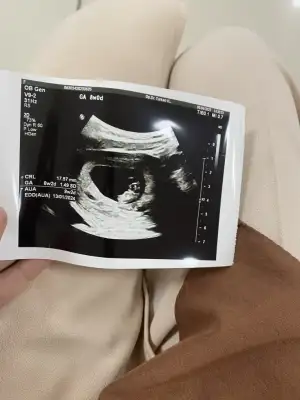

7+1 de kalp atışınıda bebişide gördük şükürŞimdi birde bebiş gözükürken varsa bi cinsiyet tahmininiz alırım bacımsular

Kesesi fasulye gibi. Fasulye gibi oluncada kız derler kuzum . Rabbım hayırlısını versın ınsallahEki Görüntüle 3260862

7+1 de kalp atışınıda bebişide gördük şükürŞimdi birde bebiş gözükürken varsa bi cinsiyet tahmininiz alırım bacımsular

İlki 6+1 yazıyo zaten, biri 7+6, en net olan doktor türkan yazan tam 8 haftalıkAnlamak değil bi teori var ramzi teorisi ona göre bakıyorum ama kesin tutuyor diyemem istersen at:)

Canım seninki de prensese benziyor içimden öyle geçti Allah gönlündekini nasip eder inşallahİlki 6+1 yazıyo zaten, biri 7+6, en net olan doktor türkan yazan tam 8 haftalık